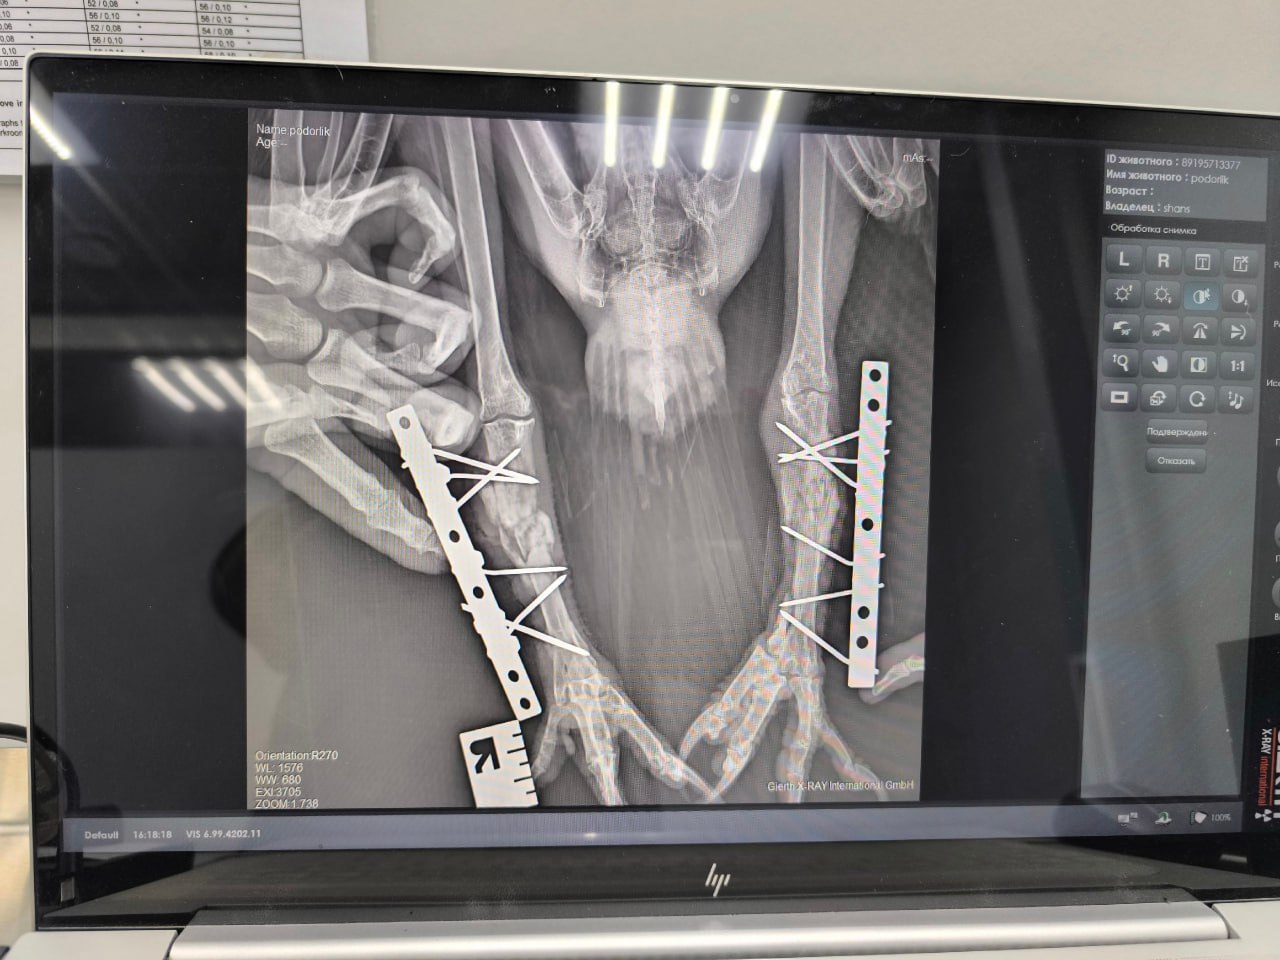

Большой подорлик попал под поезд. Редкого хищника спасли волонтёры и доктор Михаил Степанов. Во время сложной 3-часовой операции пернатому установили два аппарата Илизарова.

Сейчас птица восстанавливается под круглосуточным уходом волонтёров. Снять аппараты планируют 20 ноября. Помочь подорлику можно, поддержав волонтёров — они собирают средства на оплату операции и корм.